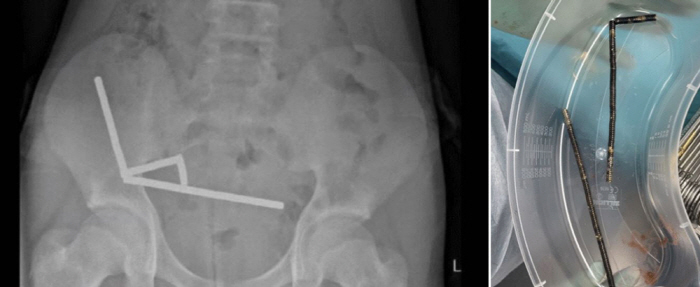

복부 엑스레이 검사 결과, 자석들이 자기력에 의해 서로 붙어 장기 내 여러 부위에 선형으로 분포되어 있었고, 이로 인해 소장과 대장의 일부인 맹장에 괴사(조직 사멸)가 발생했다.

의료진은 자석 제거와 함께 괴사 부위의 장을 절제하는 수술을 진행했고, 소년은 8일간의 치료 후 퇴원했다. 수술 날짜는 공개되지 않았다.